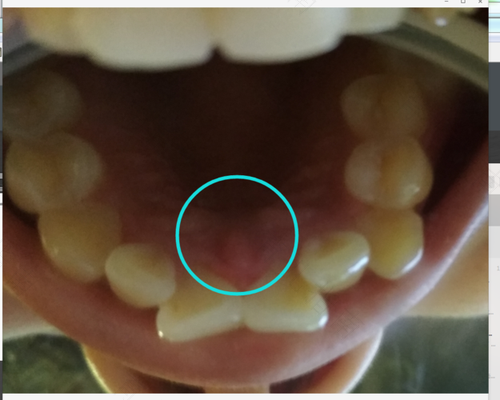

现如今,经济发展好了,人们生活富足,所吃的食物也是越来越丰富,但部分人并不注意口腔卫生健康,所以就难免会出现了一系列问题,牙龈痒是怎么回事?原因如下:

1、牙龈痒是牙龈炎的最开始的一种体现,可以每天早晚各刷一次牙,平时可以用盐水进行漱口,可以多有几次平时多吃一些新鲜的水果和蔬菜。

4、用力紧要着牙会感觉好一些,也可以用牙签的牙间隙处清理一下、出点血,也会感觉好一点,就没那么疼了,当炎症逐渐加重后,会出现咬合痛。易反复发作。